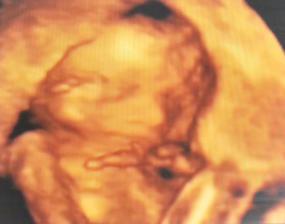

✿♥♥♥♥Bude to dievčatko!!!!! ♥♥♥♥✿

Bude to Stella 🙂

krasne 3D sono 🙂